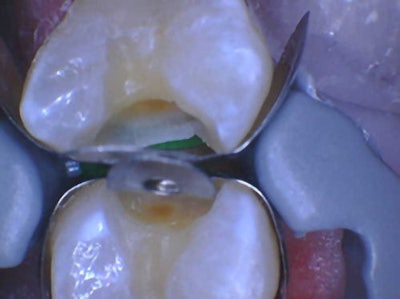

Using the same radiograph from above (Figure 8), I transilluminated the questionable areas, yielding highly accurate discernment of the extent and location of various cavities.

Figure 9: This is the interproximal space between teeth #s12 and 13. Notice that, upon learning the location of these interproximal lesions, the practitioner doesn’t have to prepare the lingual extent of the interproximal box.Figure 9: This is the interproximal space between teeth #s12 and 13. Notice that, upon learning the location of these interproximal lesions, the practitioner doesn’t have to prepare the lingual extent of the interproximal box.